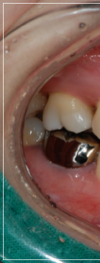

이 처럼 입을 다물어도 어금니만

맞물린 채 앞니가 맞물리지 않는 증상을

개방교합이라고 부르는데요.

개방교합은 입을 다물때 안쪽

어금니만 맞닿고 앞니 쪽은 닿지 않아

입술이 붕 떠 있는 상태를 말했어요.